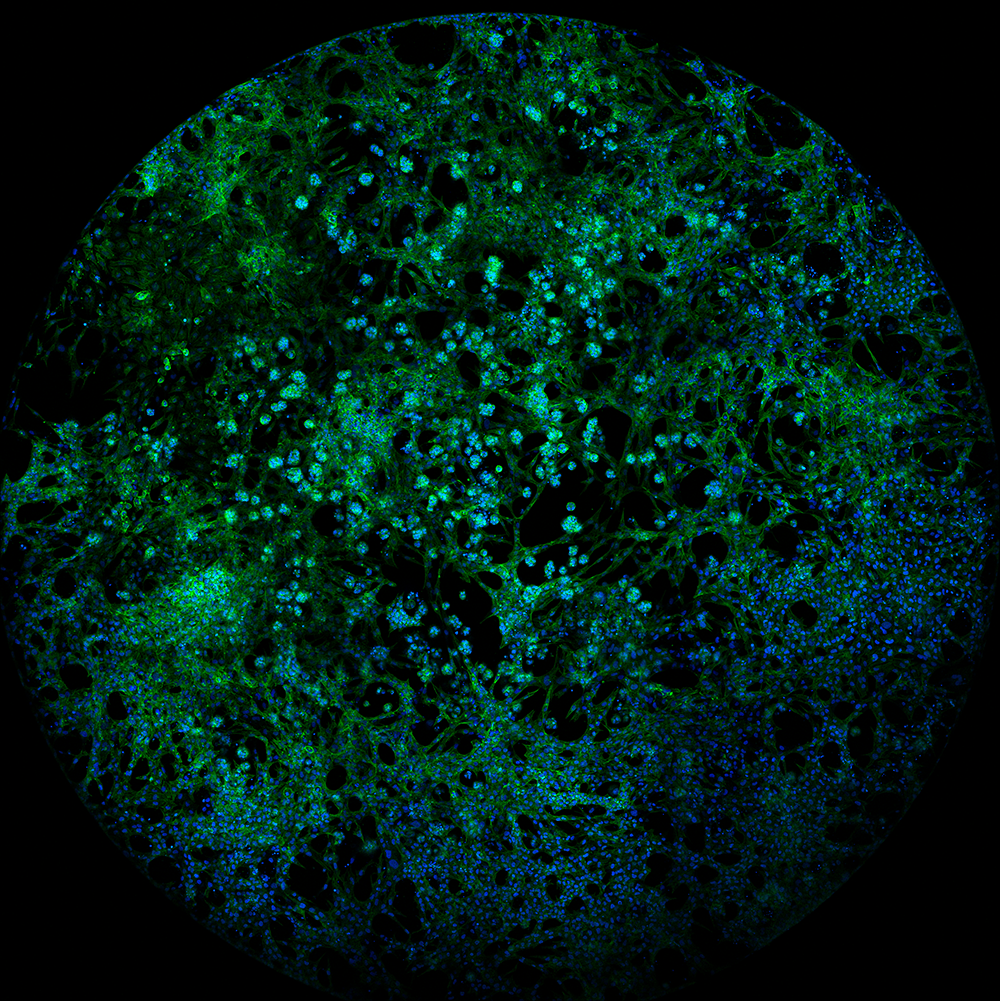

Circular microscopic-style image showing a dense pattern of green and blue speckled structures against a black background

The cellular blue planet – entered by Jasmine Kaur, PhD Student This glowing image shows human kidney cells grown in the lab. Blue marks the nuclei and green highlights the cell structure that gives each cell shape. From afar, it resembles a tiny planet. Scientists use this model to study kidney disease and test treatments that may prevent harmful cell clumping and protect kidney health.